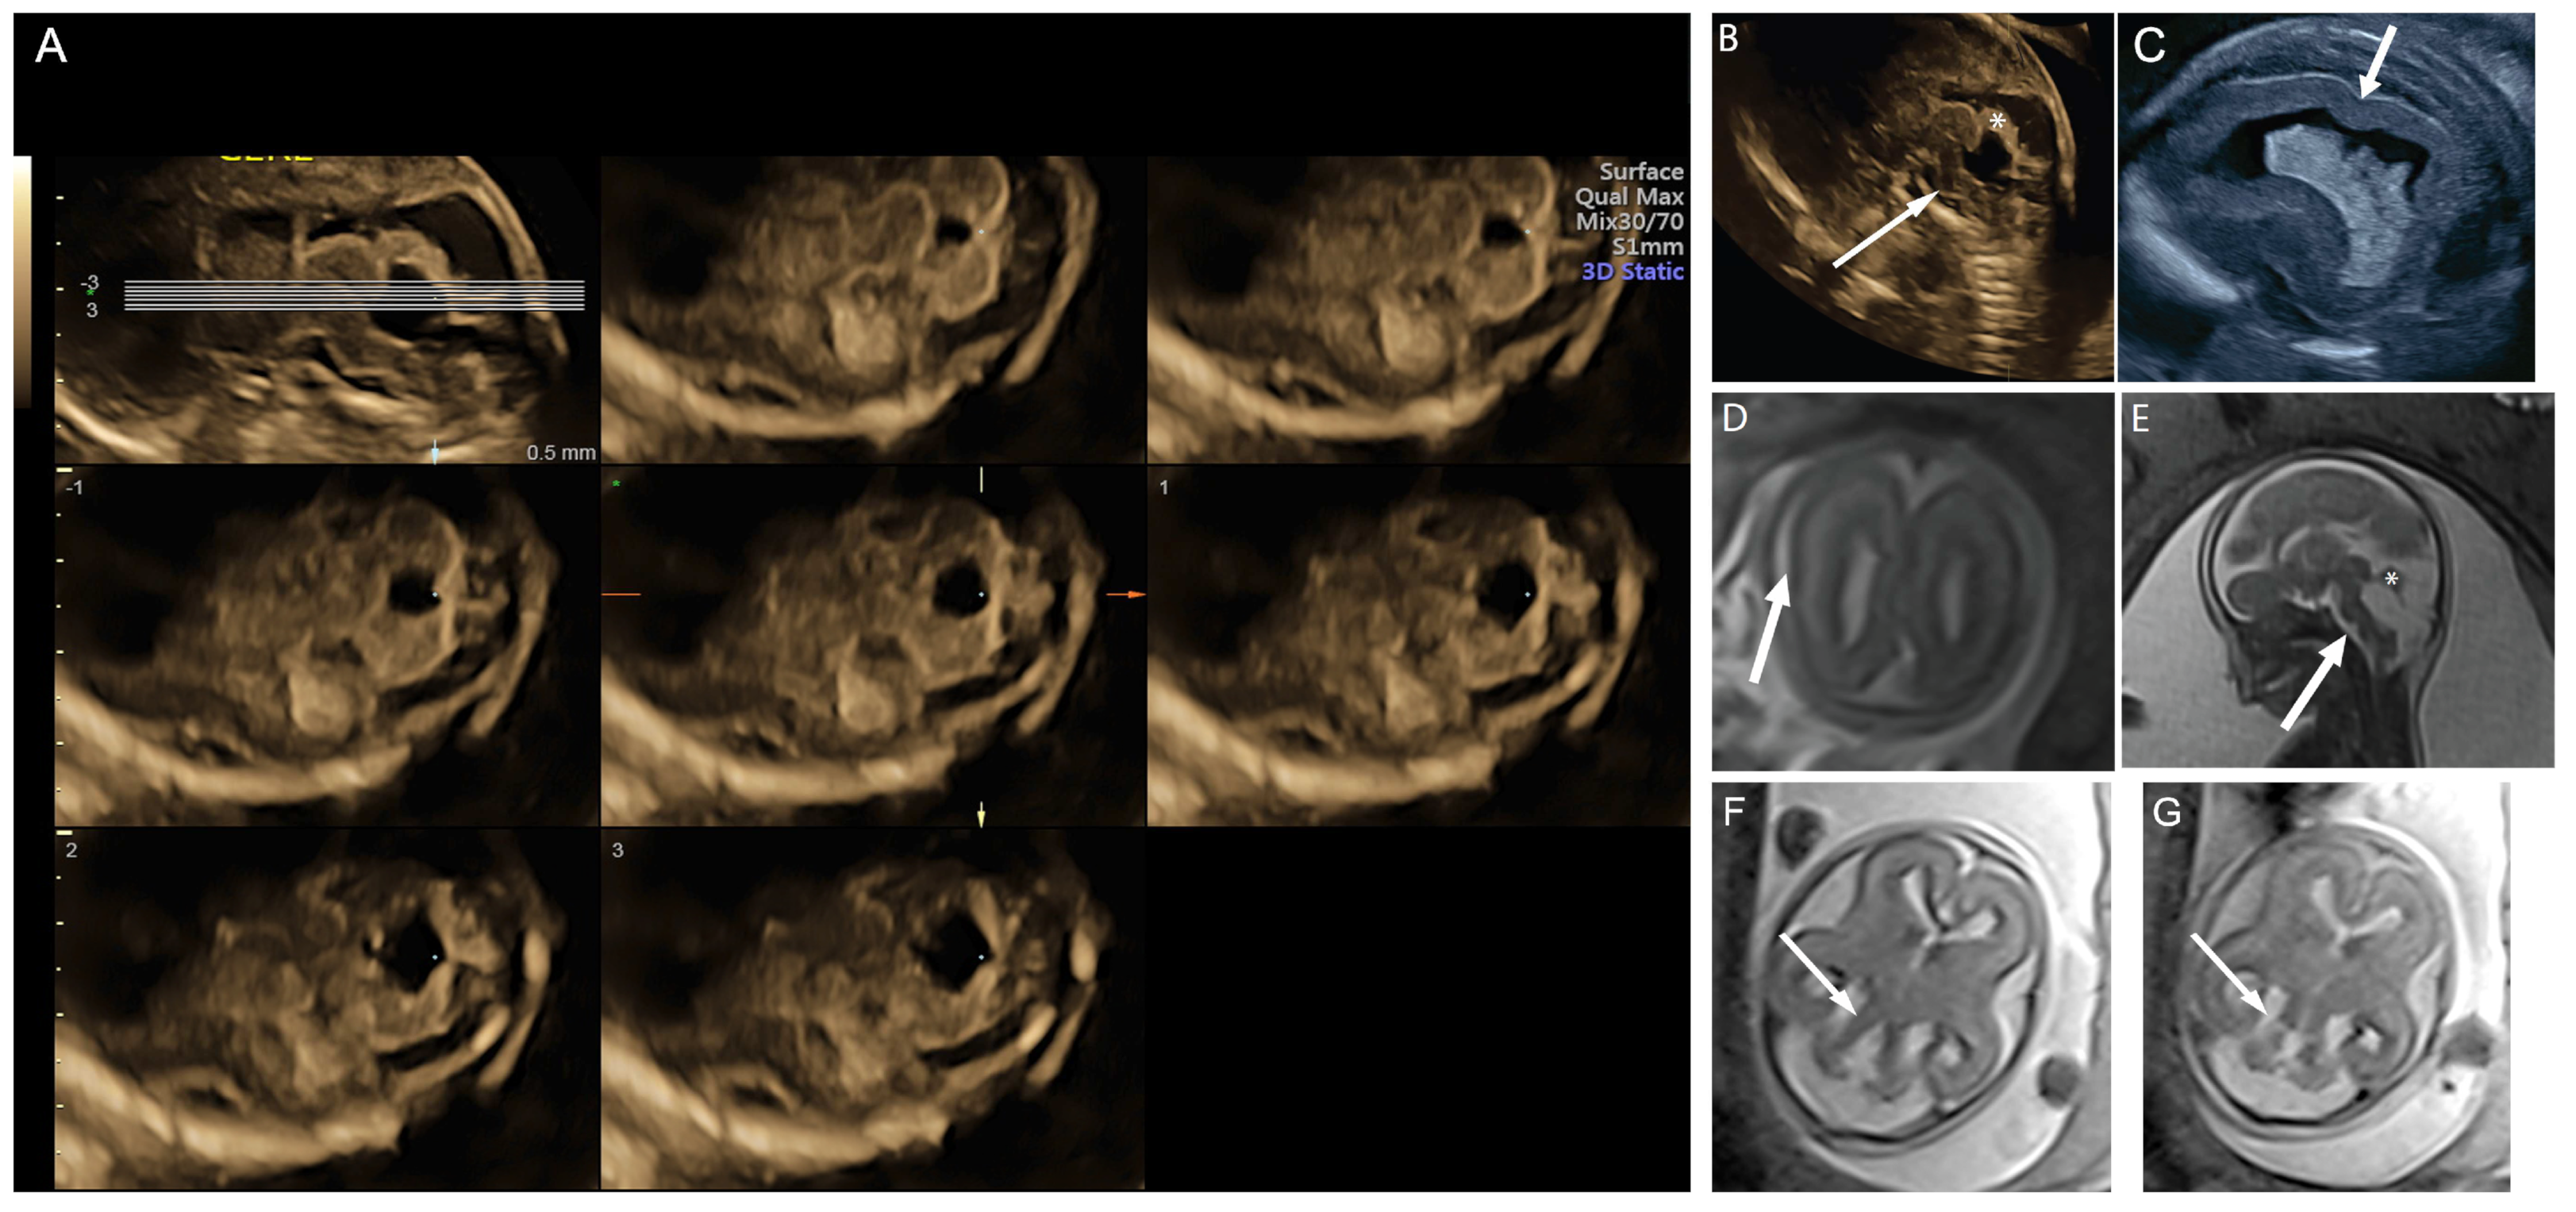

A 21-year-old G1P0 was referred at 16 weeks gestation for possible Blake’s pouch cyst. Her 12 week scan was notable for increased nuchal translucency. Neurosonogram at 16 weeks and 6 days tomographic ultrasound imaging (TUI) demonstrated splayed cerebellar hemispheres across multiple slice planes (lines = slice planes, upper left image) (A) and an abnormally rotated and dysplastic midline cerebellar structure, possibly representing the early fetal vermis (asterisk, (B)). These findings were readily differentiated from the referring diagnosis of Blake’s pouch cyst when additional ultrasound findings of hypersuclated parietal cortex, consistent with polymicrogyria (arrow, (C)) and hypoplastic brainstem (arrow, (B)), were also identified. Microarray was normal. MRI performed at 20 weeks and 4 days confirmed the ultrasound findings of polymicrogyria (arrow, (D)), abnormal brain stem (arrow, (E)), and hypoplastic and abnormally rotated midline cerebellar structure (asterisk, (E)). Thick and abnormal-appearing cerebellar peduncles were also noted (arrows, (F,G)). The patient elected termination. Trio exome sequencing revealed a compound heterozygous variant in PIBF1 in the fetal specimen, which is consistent with a diagnosis of Joubert syndrome 33.